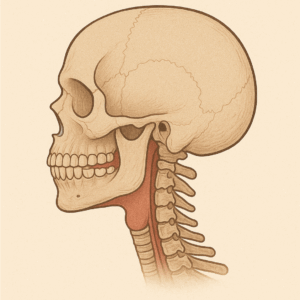

MRCシステムでは顔(あご)を前に成長させるようにあの手この手を使いますが、これがいわゆる「システム」に埋め込まれているのです

ここで②の厚みのある装置のメリットとデメリットが関わってくるのですが、大きなデメリットしては下顎を後退させてしまう可能性です

(AI作成)

(AI作成)